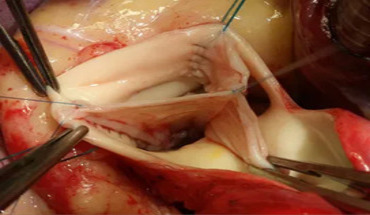

BioZone is a medical supplies company specializing in advanced, high-quality equipment and consumables for cardiac, vascular, electrophysiology (EP) surgeries, and other medical interventions. The company sources its products from leading global manufacturers and ensures they meet the needs of healthcare providers with the latest technology and innovation. BioZone focuses on offering equipment and consumables that enhance patient care, streamline surgical processes, and ensure procedural success.